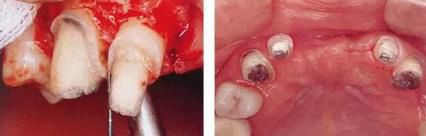

▲圖7-1

對(duì)上頜前牙進(jìn)行初期治療后的咬合面觀。右上2,3存在炎癥。

▲圖7-2,3

▲圖7-2 齦瓣剝離后,可以看到右上3近中側(cè)沉積著大量牙結(jié)石。由于牙根接近而無(wú)法用刮匙除去

▲圖7-3  牙周外科處理后的愈合期狀態(tài)。右上2,3之間愈合形成了充分的角化齦。